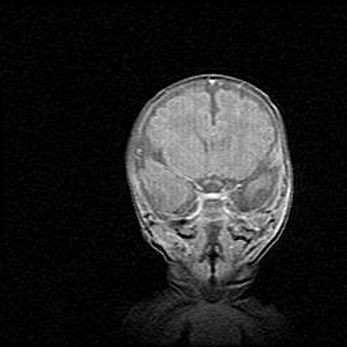

Открытая гидроцефалия.

Возраст: 9 месяцев 12 дней

Вес: 6800 г

Пол: мужской

Окружность головы: 41,5 см

Срок гестации: 28 недель

Гидроцефалия головного мозга у новорожденных имеет характерный признак: опережающий рост окружности головы приводит к визуально хорошо определяемой гидроцефальной форме сильно увеличенного в объёме черепа. Детские неврологи определяют следующие симптомы гидроцефалии у грудничков: выбухающий напряжённый родничок, частое запрокидывание головы, смещение глазных яблок к низу.